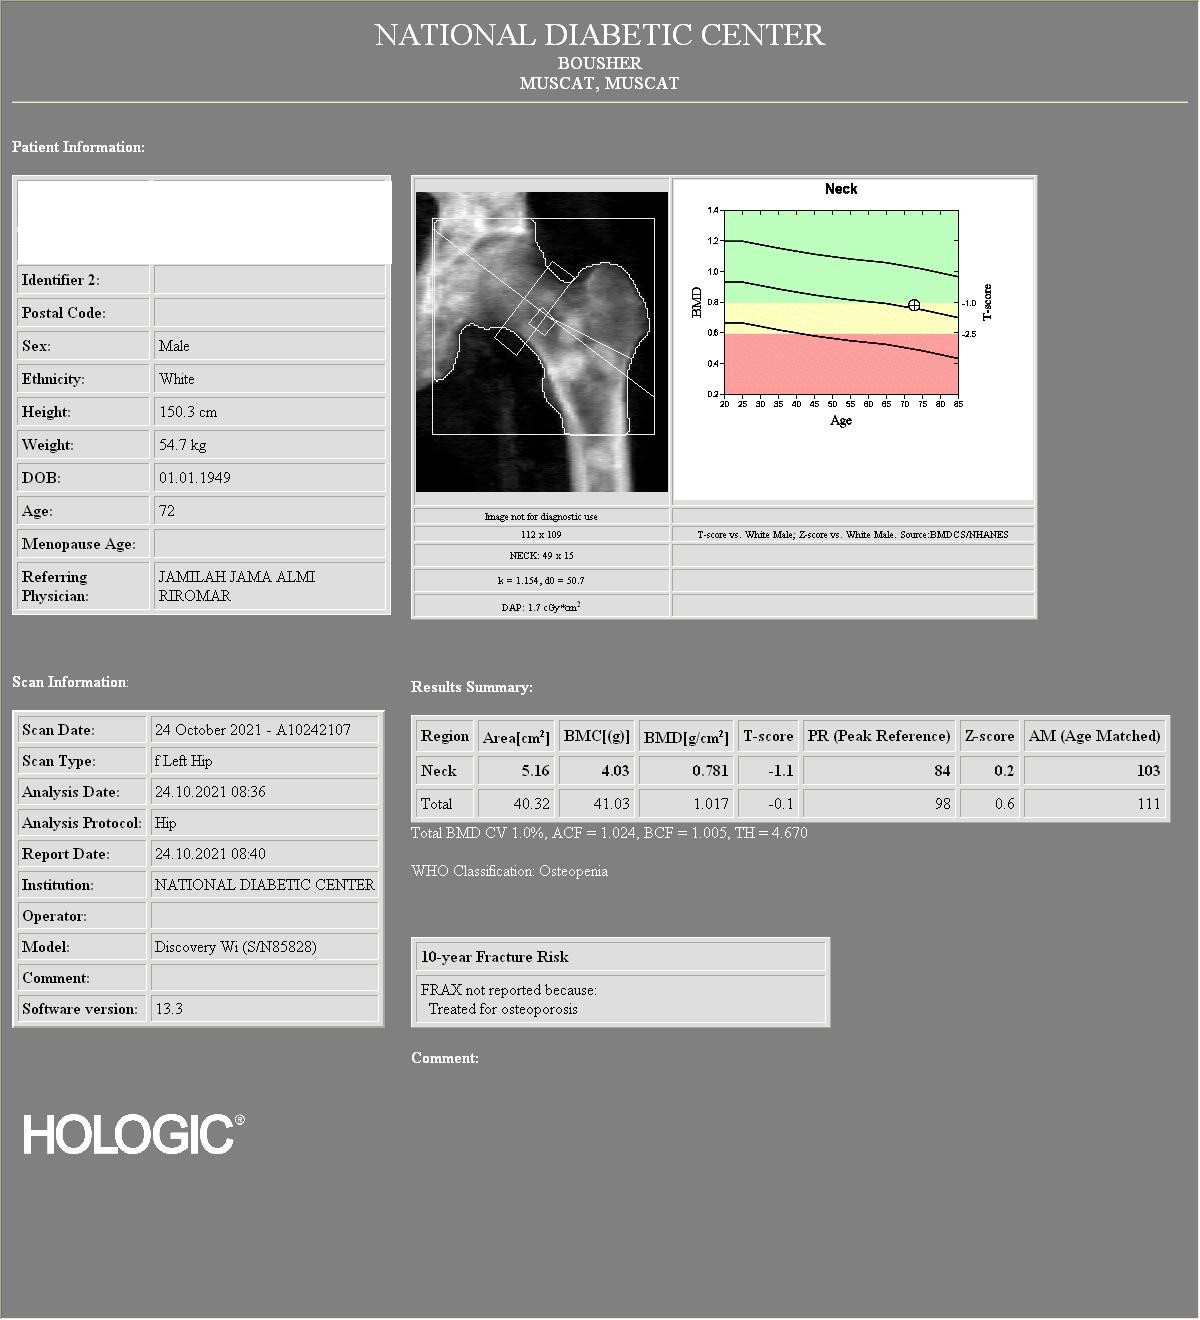

Bone density analysis of the left hip

72 years old male patient a newly diagnosed case of hormone sensitive metastatic prostate cancer. BMD study was done to evaluate for bone density status.

The BMD machine used is Hologic, model: Discovery Wi (S/N85828)

The non diagnostic image of the left hip used for BMD analysis showed ill-defined rounded sclerotic lesions in the femoral neck and proximal shaft of the left femur.

The T-score of the left femoral neck was -1.1, and the total left hip T-score was -0.1

From the non diagnostic lumbar spine and left hip images used for BMD analysis, its clear that there are diffuse bone sclerotic lesion/metastasis, and hence we requested our radiographer to do BMD measurement from the left forearm which showed significant reduction in bone density with distal third of radius T-score of -7.0

We reported the study with diagnosis of osteoporosis based on the left forearm findings and we mentioned that the BMD and T-score values of the lumbar spine and left hip are falsely high due to diffuse sclerotic bone lesions.